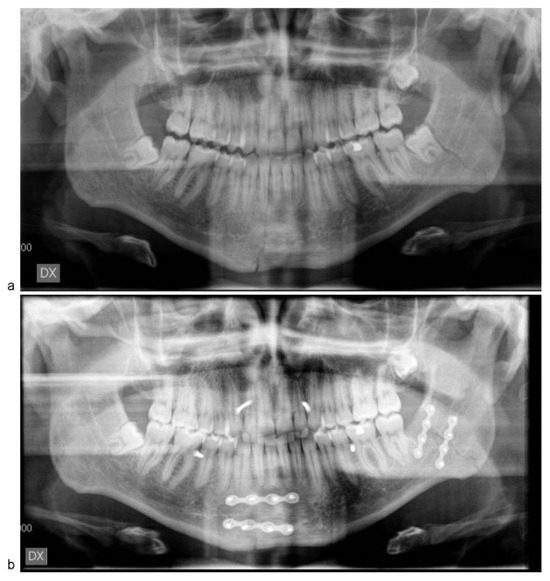

![]() |